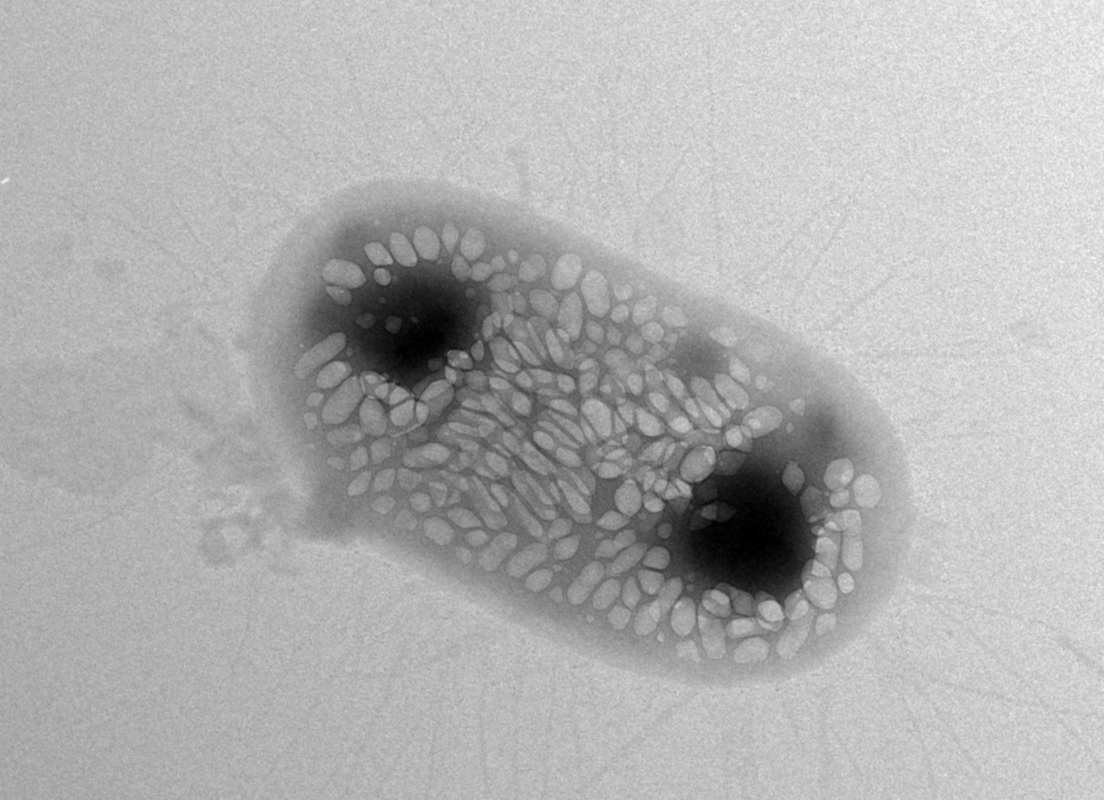

Shapiro wants to solve this problem with ultrasound techniques because sound waves can travel deeper into bodies. He says he had a eureka moment about six years ago when he learned about gas-filled protein structures in water-dwelling bacteria that help regulate the organisms' buoyancy. Shapiro hypothesized that these structures, called gas vesicles, could bounce back sound waves in ways that make them distinguishable from other types of cells. Indeed, Shapiro and his colleagues demonstrated that the gas vesicles can be imaged with ultrasound in the guts and other tissues of mice.

One of the challenges the team hit involved the transfer of the genetic machinery for gas vesicles into E. coli. They first tried to transfer gas-vesicle genes isolated from a water-dwelling bacterium called Anabaena flos-aquae, but this didn't work—the E. coli failed to make the vesicles. They tried again using gas-vesicle genes from a closer relative of E. coli, a bacterium called Bacillus megaterium. This didn't succeed either, because the resulting gas vesicles were too small to efficiently scatter sound waves. Finally, the team tried a mix of genes from both species—and it worked. The E. coli made gas vesicles on their own.

The gas vesicle genes code for proteins that act like either bricks or cranes in building the final vesicle structure—some of the proteins are the building blocks of the vesicles while some help in actually assembling the structures. "Essentially, we figured out that we need the bricks from Anabaena flos-aquae and the cranes from Bacillus megaterium in order for the E. coli to be able to make gas vesicles," says Bourdeau.

Subsequent experiments from the team demonstrated that the engineered E. coli could indeed be imaged and located within the guts of mice using ultrasound.